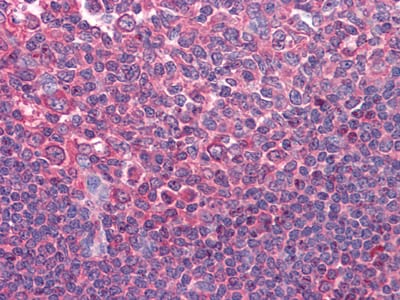

分类: 科研抗体货号: 20354别名: KIA; Ki-67; MKI67应用: IHC,IF反应种属: Human,Mouse,Rat,Rabbit,Monkey

-